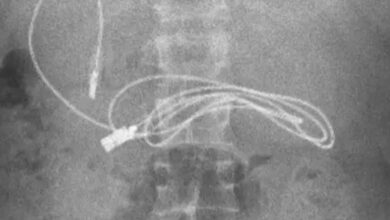

Descubren que un menor de 15 años tenía un cable USB en el estómago: «Un extremo había pasado al intestino»

Un menor de 15 años acudió a urgencias al sufrir fuertes dolores estomacales. Tras realizar varias pruebas, los médicos descubrieron…